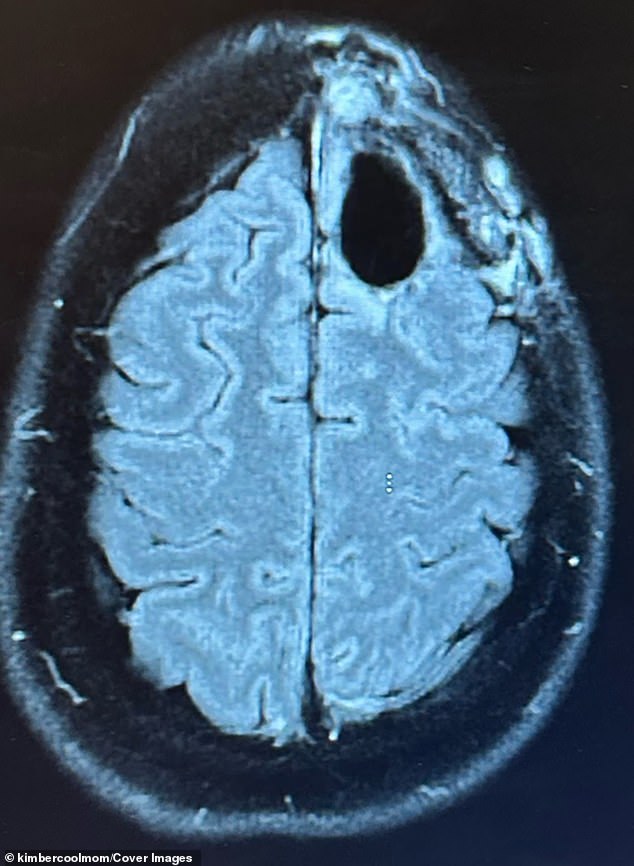

Kimberly Pelling's story is a harrowing blend of medical horror and personal resilience. Diagnosed with grade-four IDH-mutant anaplastic astrocytoma in August 2022, just four months after giving birth, she was told she had at most three years to live. The tumor, located in her frontal lobe, was aggressive and typically incurable. It began stealing her concentration, memory, and even parts of her personality. 'Nothing prepares you for that moment,' she said. 'It was devastating.'

Her journey began with night terrors that led to an MRI revealing a lime-sized tumor. The biopsy confirmed the worst: grade-four astrocytoma, a type of brain cancer with a median survival of around 31 months. But Pelling's story took a different turn. After her initial treatment failed, she pivoted to a carnivore diet, relying on grass-fed beef, eggs, and butter, while eliminating sugar. She also adopted a regimen of supplements, including methylene blue, curcumin, and melatonin, each chosen for their purported anti-cancer properties.

In 2025, a routine scan delivered news that defied her original prognosis: no evidence of cancer. 'I walked into that appointment prepared for anything,' she said. 'Hearing there was no evidence of cancer felt surreal.' Yet she remains cautious. 'The cancer might come back,' she acknowledges. 'But today, I'm too busy living to worry about dying.'